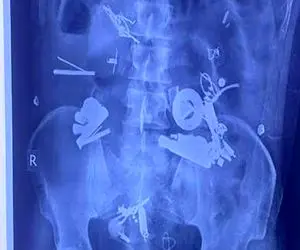

مجموعهای از اجسام خارجی در شکم او وجود داشتند. پس از جراحی، پزشکان ۱۵۰ قلم شئ از جمله دستبند، زیپ، میخ و پیچ و مهره…